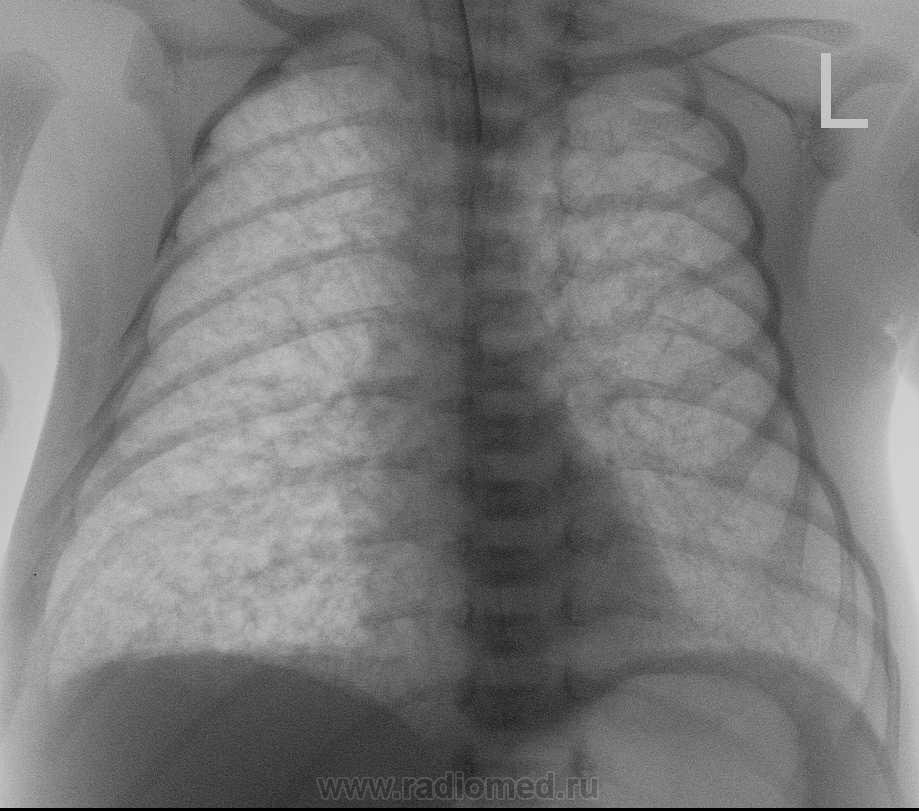

Снимок от 5.03.10г.

Трудно сказать, но мысли в пользу интерстециальной пневмонии, преимущественно вирусной этилогии, однако ребенку провели курс антибактериальной терапии, на данный момент он самостоятельно дышит, клиники ни какой нет, динамика положительная. Во время прведения курса лечения 9.03. был сделан рентген-контроль, где  динамика положительная была.

1.По диссеминации похоже динамика положительная.

2.Но не складывается ли впечатление о появлении сливной инфильтрации справа в базально-медиальном отделе, ближе к корню?

3.В нерешительностиВозможно присоединение бактериального компонента на фоне вирусного поражения....

Стараюсь вообщем то отслеживать ход демонстрируемых случаев, но поскольку поток пациентов вариабильный, ни как не могу сконтактироваться с неонатологами, на данный момент по электронной истории, состояние средней тяжести связано с незрелостью ребенка. По снимку в динамике хочу согласиться с Вами что есть затемнение в прекорневой зоне справа, однако по поводу забора анализов ПЦР на ЦМВ, мне не известно.